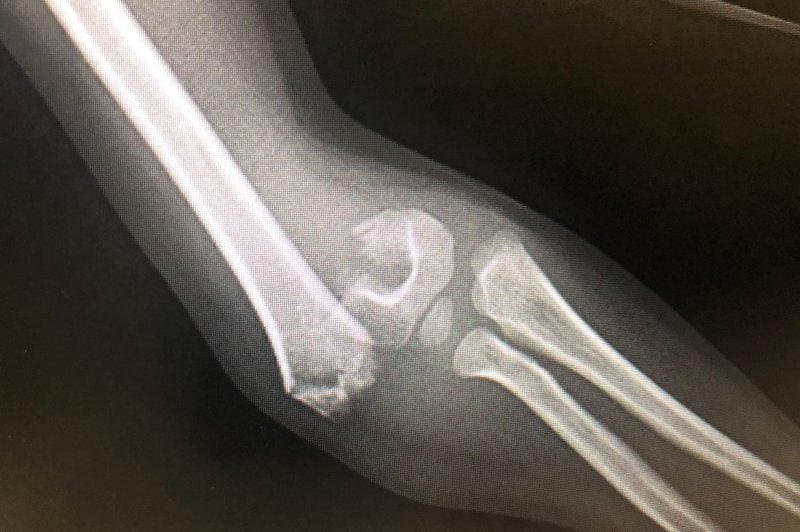

Kết quả thu được cho hình ảnh thấy được các cấu trúc giải phẫu của hệ thống xương chi, giúp bác sĩ phát hiện được tổn thương và đánh giá được tính chất ngấm thuốc cản quang nếu có.